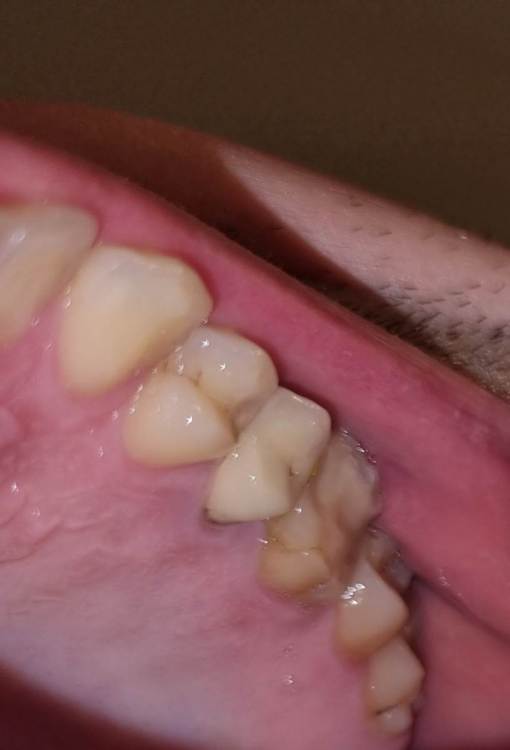

Chelovek2012 Опубликовано 17 апреля, 2023 Поделиться Опубликовано 17 апреля, 2023 (изменено) Всем добрый день. У меня вопрос. Верхняя левая 6-ка: Зуб давно был с запломбироваными каналами. Месяц назад их перепломбировали. Вкрутили в середину зуба какие-то как шурубчики для укрепления. И доктор говорит, что будет коронка Можно ли поборотся и спасти зуб, в который уже вкручены шурупчики для укрепления? 3 стенки зубы точно вижу на фото. Или нету смысла и он разлетится? Пломбировать уже нету смысла? Или технология пломбирования уже тут не подходит? 5 зуб возле него. Врачь говорит сразу сменить и эту коронку (ей 10 лет), так как между зубами есть нестыковка - темное место на рентгене между зубами Изменено 17 апреля, 2023 пользователем Chelovek2012 Ссылка на комментарий

DoctorT Опубликовано 18 апреля, 2023 Поделиться Опубликовано 18 апреля, 2023 (изменено) Коронка и ставиться, чтобы побороться за этот зуб, в противном случае (при таком объеме пломбы) вы его потеряете рано. Кстати, если вы перепроверяете слова вашего доктора, рекомендую вам сменить доктора на того, кому вы будете доверять. Изменено 18 апреля, 2023 пользователем DoctorT Ссылка на комментарий

DoctorT Опубликовано 19 апреля, 2023 Поделиться Опубликовано 19 апреля, 2023 1 час назад, Chelovek2012 сказал: А это касается и других зубов, у которых есть только стенки? Нету технологии спасти зуб (во своих стенках) без коронки? Вы не бойтесь коронки, они же бывают разные, главное сделать грамотно и чтобы прилегание было отличное, такая коронка может прослужить очень долго. Поймите, что если убрать весь пломбировочный материал с зуба, то от него ничего не останется. Коронка только армирует ваши оставшиеся стенки и пломбу, как деревянную бочку армируют железные кольца... 1 Ссылка на комментарий